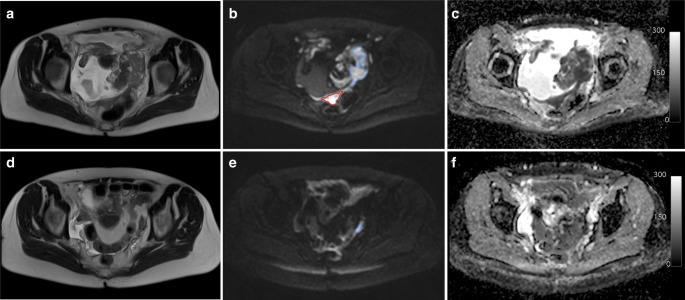

Diffusion-weighted (DW)- MRI, developed for brain imaging more than a decade ago, derives image signals from the movement of water molecules, mainly within the spaces outside cells. The less freely water can move-for example in cancer tissues where cells are crowded together and the space around them is limited- the more signal is retained in DW-MRI, and the brighter the tissue appears.

The study looked at the numerical data within tumour nodules derived on DW-MRI scans of the abdomen and pelvis in epithelial ovarian cancer. In the first instance we sought to establish how repeatable the derived measurement-the Apparent Diffusion Coefficient (ADC)- was when made at multiple hospitals using different MRI scanners. We did this by scanning the same patient twice before they started their chemotherapy and showed that the ADC measurements (recorded as a median value from all voxels in the region-of-interest, ADCmedian) were more repeatable than lesion volume measurements: in ovaries, peritoneum (lining membrane) and omentum (fatty apron covering the abdominal organs) the limits of agreement were within 20% of the absolute mean value, (within 30% for lymph nodes) for the 2 repeat ADC measurements. In comparison, limits of agreement for lesion volume were often >50% of the absolute mean value on repeat measurement.

With this in mind, we went on to show that after 3 cycles of chemotherapy, in tumour nodules that remained measurable (comprising >10 voxels), 28 of 40 ovarian, 24 of 50 peritoneal, 8 of 27 omental and 17 of 22 lymph node lesions increased in ADCmedian above the upper Limits of Agreement. We wanted to understand what an ADC increase after chemotherapy equated to at a histological level. So following removal of the nodules at scheduled surgery, we matched the imaged nodules with the surgically excised nodules and then trained a computer algorithm based on detailed annotations by a pathologist to recognise remaining viable and necrotic (dead) tumour. We found that increase in ADC from baseline correlated with the amount of necrotic tumour, and that this correlation was predominantly because of the peritoneal nodules. Also, the absolute values of ADC on the pre-surgical scans (taken after neoadjuvant chemotherapy) correlated with the amount of residual tumour in the sample, and this also was predominantly because of the peritoneal lesions.